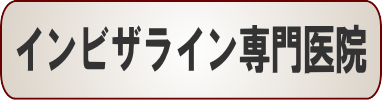

☆デコボコ症例(華 華様 52歳 女性)

▼患者様の感想

長い間のコンプレックスをわずか1年で実現させて頂けたことに感謝しています。

治療中、ほとんど誰にも気づかれなかった事が本当に嬉しい。

残念ながら、少し歯が変色した事があり(今はだいぶ元に戻りましたが)不安に感じたことも事実ですが、全体的にはいつも親身にいろいろアドバイスして頂いたと思っております。

痛みも考えていたよりも重くなくすみ、それよりも笑顔を褒められるようになった事が嬉しいです。

ありがとうございました。